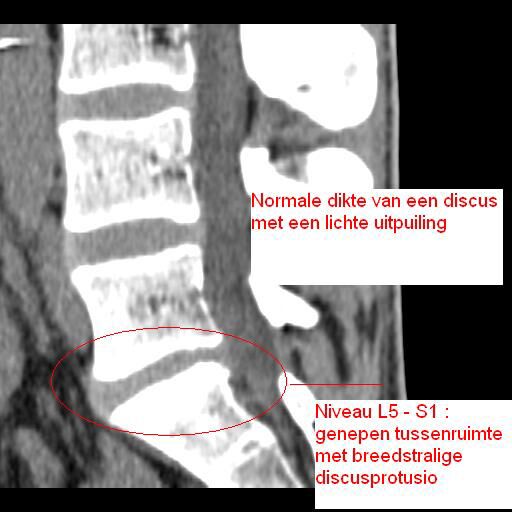

Klik hier om een link te hebben waarmee u dit artikel later terug kunt lezen.Resultaten CT-scan

Hiernaast de foto van de CT-scan (op foto klikken om meer details te zien).

Conclusie:

Een wat toegenepen discus met uitpuiling (discusprotrusio) aan de achterkant van de rug (rechterkant van de ruggegraat).

Om het in verstaanbare taal te zeggen, ik zit in het stadium voor een hernia. Bij een hernia scheurt de discus dan open en komt er discusmaterie tegen je zenuwen te drukken, wat de pijn en de uitraling veroorzaakt.